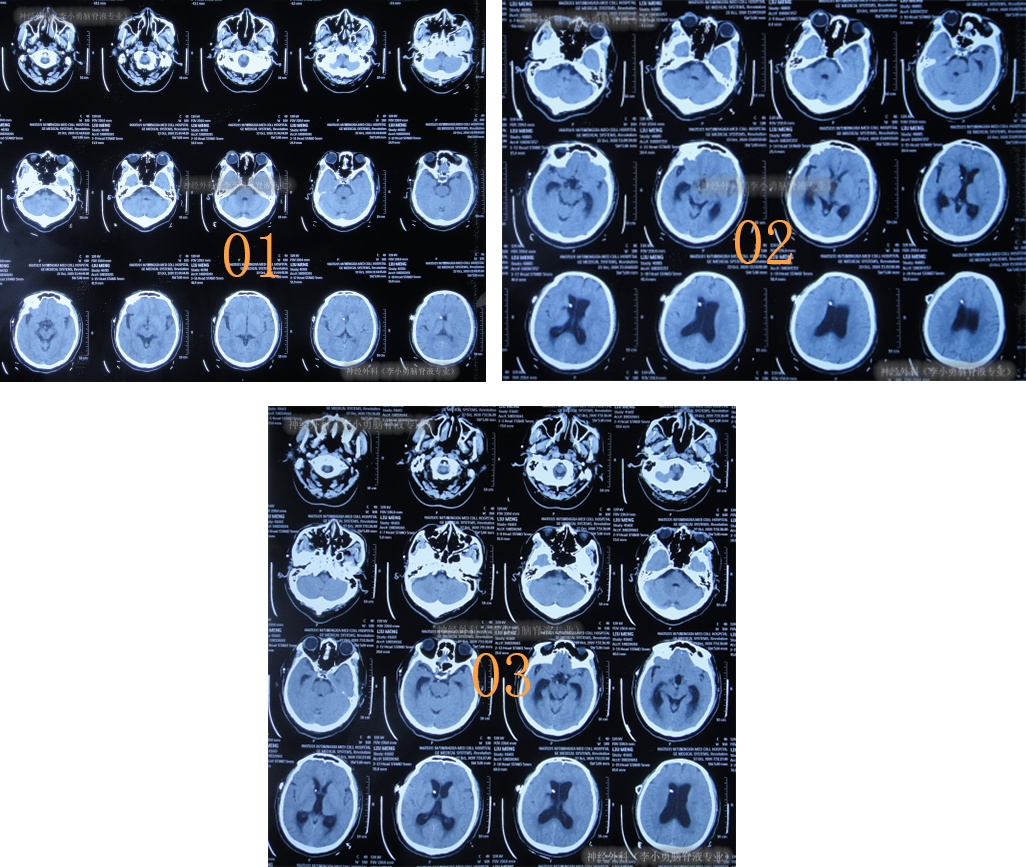

但出院后1个月即2020年12月6日(脑室腹腔分流术后3年零2月),再次出现嗜睡,第3次就诊该院,查头颅CT(片子丢失)后认为脑室系统与1月前相比并未明显扩张,但第2天即2020年12月7日,出现昏迷,大小便失禁,再查头颅CT(图-3)后认为脑室有大。

图-3:2020年12月7日头颅CT

术后次日查头颅CT示脑室有缩小(图-4),意识也有好转。

图-4:2020年12月9日头颅CT